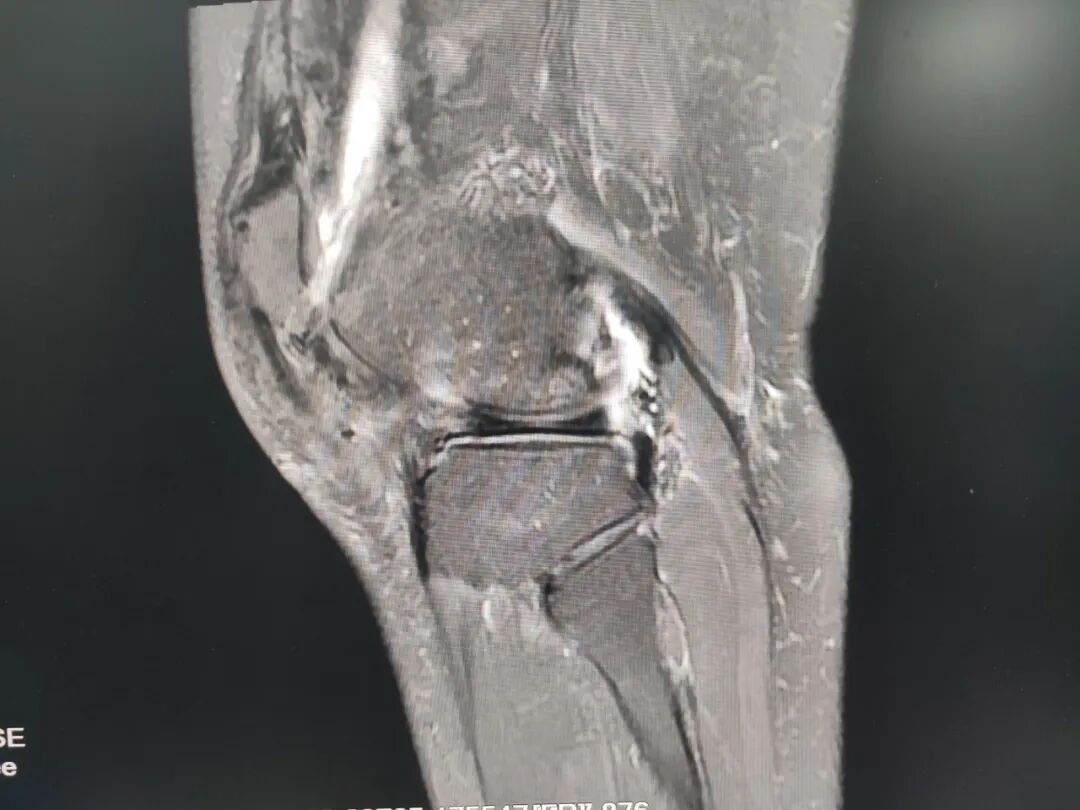

精准,是治疗的关键